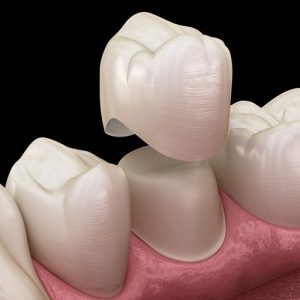

روکش دندان

استفاده از انواع روکش دندان ، یکی از بهترین روش ها به منظور داشتن لبخندی زیبا به شمار می رود. این روش، برای افرادی که دندان هایشان لک دارد، خرد شده است و یا بین دندان هایشان فاصله وجود دارد.